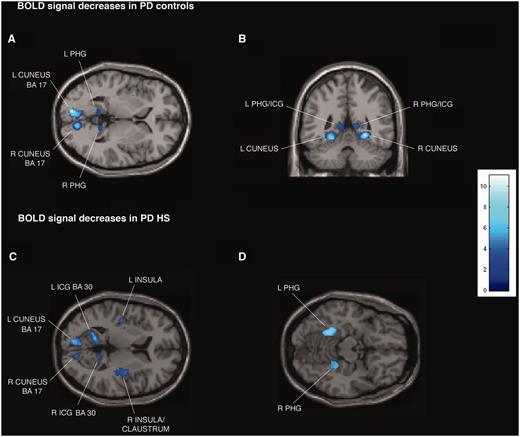

Transverse and coronal sections of statistical parametric maps showing significant BOLD signal decreases (dark and light blue areas) associated with exposure to common sexual imagery in 12 Parkinson’s disease (PD) control patients (A and B) and in 12 patients with Parkinson’s disease with hypersexuality (HS) (C and D) during the OFF medication state. BOLD signal decreases are illustrated in (A and B) left and right parahippocampal gyrus (PHG), isthmus of cingulate gyrus (ICG) and cuneus (x = −9, y = −47, z = 2), (C) left and right parahippocampal gyrus, cuneus, isthmus of cingulate gyrus, insula and right claustrum (x = −42, y = 14, z = 8), and (D) left and right parahippocampal gyrus (x = 22, y = 38, z = −14). In the ON medication state, in the group of 12 patients with Parkinson’s disease with hypersexuality, no BOLD signal decreases are detected. The colour bar indicates z-values.

Patients with Parkinson’s disease with hypersexuality and Parkinson’s disease control patients showed similar significant BOLD signal increases during exposure to sexual versus neutral visual cues in both ON and OFF medication states bilaterally in middle temporal gyrus and middle occipital gyrus (Fig. 1A and B; Supplementary Tables 2A and C, Supplementary DataA and C). For the same contrast in the OFF state, patients with Parkinson’s disease with hypersexuality and Parkinson’s disease control patients showed similar significant BOLD signal decreases bilaterally in isthmus of cingulate gyrus [Brodmann area (BA) 29 and 30], parahippocampal gyrus and cuneus (BA 17) (Fig. 2A and B; Supplementary Tables 2B and D, Supplementary DataB and D).

Whole-brain analysis confirmed the region of interest results and showed additional significant BOLD signal increases in the group of patients with Parkinson’s disease with hypersexuality compared with Parkinson’s disease control patients during exposure to sexual versus neutral visual cues in the OFF and ON medication states in the following regions: bilateral anterior prefrontal cortex (BA 10) and superior parietal lobule (BA 5 and 7), and right lateralized activation in the inferior parietal lobule (BA 40) (Fig. 1C–H; Supplementary Tables 2A and C, Supplementary DataA and C). For the same contrast in the OFF state, patients with Parkinson’s disease with hypersexuality compared with Parkinson’s disease control patients showed significant BOLD signal decreases bilaterally in insula and right claustrum (Fig. 2C and D; Supplementary Tables 2B and D, Supplementary DataB and D). There were no different BOLD signal increases during exposure to sexual versus neutral visual cues in patients with Parkinson’s disease with hypersexuality between the OFF and ON medication states.

In the group of patients with Parkinson’s disease with hypersexuality in the ON medication state, the decreases observed in the OFF state and in the OFF and ON state in Parkinson’s disease control patients (reduced BOLD signal during exposure to sexual versus neutral visual cues in isthmus of cingulate gyrus, parahippocampal gyrus, cuneus, insula and claustrum) were eliminated (Supplementary Tables 2B and D, Supplementary DataB and D).

Interestingly, in the group of patients with Parkinson’s disease with hypersexuality after acute l-DOPA challenge, the decreases observed when OFF their drugs and in the OFF and ON state in Parkinson’s disease control patients (reduced BOLD signal during exposure to sexual versus neutral visual cues in isthmus of cingulate gyrus, parahippocampal gyrus, cuneus, insula and claustrum) were eliminated (for a similar effect of dopaminergic drug challenge in cocaine addiction, see Volkow et al., 2010). These results suggest that dopamine drugs could eliminate the deactivation of brain regions, which may be related to plastic changes in an effort to inhibit hypersexuality stimulation. Although it is difficult to translate excitation or inhibition of neuronal firing into BOLD signal increases or decreases in activated voxels (Georgopoulos et al., 1982; Batini et al., 1984), dopamine drugs could release this inhibition through the activity of inhibitory interneurons acting within local neuronal circuits in the cerebral cortex. The release of neuronal inhibition in the isthmus of cingulate gyrus, parahippocampal gyrus, cuneus, insula and claustrum when patients are ON their dopaminergic drugs could be associated with concurrent behavioural changes as in this study was an associated increase in sexual desire scores. This theory is supported by the complete cessation of hypersexuality after withdrawal from dopamine receptor agonist medications (Mamikonyan et al., 2008; Munhoz et al., 2009).